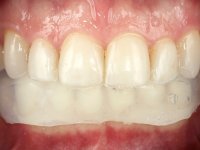

Paciente do sexo masculino, com 36 anos, não fumador. Fez tratamento ortodôntico e reabilitou esteticamente o sector anterior com restaurações em resina composta. As restaurações apresentavam um aumento vertical médio de 2 mm em relação o bordo incisal. Apresentavam-se esteticamente satisfatórias, mas com algumas fraturas incisais. O dente 1.5 apresentava um processo apical e o dente 2.6 apresentava tratamento endodôntico e uma lesão endo-periodontal. No maxilar inferior no local do dente 3.5 apresentava um implante com uma coroa aparafusada e o dente 8.5 ainda estava presente em boca com agenesia do dente 4.5. O paciente apresentava uma ligeira perda da dimensão vertical da oclusão provavelmente associada a um visível desgaste das superfícies oclusais. O periodonto era espesso e apresentava uma excelente higiene oral.

Após análise clínica e imagiológica foi proposto ao paciente recuperar a dimensão vertical da oclusão essencialmente à custa de incrementos oclusais inferiores utilizando “overlays” no sector posterior e facetas no sector anterior. A coroa aparafusada sobre o implante 3.5 seria substituída, no sentido de acompanhar este incremento. Na maxila o dente 2.6 teria extração indicada e posteriormente seria reabilitado com um implante e respetiva coroa. No sentido de reabilitar esteticamente o paciente duma forma minimamente invasiva, foi proposta a colocação de facetas feldespáticas no sector antero-superior. O objetivo de aumentar ligeiramente a D.V.O., teria como função “proteger” eficazmente o sector antero-superior.

Realizado o diagnóstico e tomada a decisão quanto ao tratamento a executar, tornou-se importante definir qual a sequência de trabalho a adotar no sentido de conseguir a reabilitação da D.V.O. (V.D.O), de forma progressiva e equilibrada. Na primeira fase fez-se uma pré-impressão da arcada inferior com silicone tipo “putty” e em seguida realizou-se o preparo dentário de todo o sector posterior. O preparo para os overlays foi feito coronalmente à linha amelo cementaria no sentido de ser o mais conservador possível. A impressão foi feita com técnica de dupla mistura após afastamento gengival realizado com pasta de caulino. A provisória foi realizada com resina composta de polimerização dual. Em laboratório foram realizados os overlays após se ter aberto ligeiramente (1,5mm) a D.V.O. nos modelos montados em articulador semi-ajustável. Simultaneamente o sector antero-inferior foi encerado no sentido de acompanhar este aumento da D.V.O. Também foi confecionada uma chave de silicone translucido para posterior confeção dos provisórios antero-inferiores. Em boca foi primeiro realizada a provisionalização dos dentes anteriores utilizando resina composta previamente aquecida após preparação das superfícies dentárias para a adesão. Foi colocado o dique de borracha para promover o isolamento absoluto e posteriormente foram colados os overlays. Em laboratório foi realizada nova chave de silicone para confecionar os provisórios antero-superiores. Seguidamente em boca foram preparados os seis dentes antero-superiores após colocação do fio de afastamento gengival. Feita a preparação adequada das superfícies dentárias foi realizada a impressão com técnica de dupla mistura e a respetiva provisória. Em laboratório foram confecionadas 6 facetas feldespáticas num modelo de trabalho tipo “Geller”. A provisória foi removida e as facetas foram coladas em boca utilizando um isolamento relativo competente. Esta opção foi tomada em virtude de uma prévia experiencia negativa com a colocação do dique de borracha na mandibula. Após a colagem dos laminados antero-superiores foram dadas 12 semanas para avaliar a adaptação do paciente à nova situação e então iniciar a confeção das facetas antero-inferiores. Após colocação do fio de afastamento gengival. foram feitos os preparos dentários adequados e em seguida foi feita a impressão. Também foi feita a preparação do dente 3.4 que, entretanto, tinha sofrido uma fratura do overlay. As facetas e a restauração do 3.4 foram realizadas num modelo de trabalho tipo “Geller”. Após remoção da provisória, as facetas foram coladas em boca, utilizando um isolamento relativo pelas razões apontadas anteriormente. Após colocação do trabalho o paciente foi reabilitado por outros colegas com um implante na zona do 2.6 e substituição da coroa aparafusada sobre o implante colocado no local do 3.5. Posteriormente surgiram fraturas nos overlays dos dentes 4.7 e 3.7 que foram reabilitados com overlays em Zr.